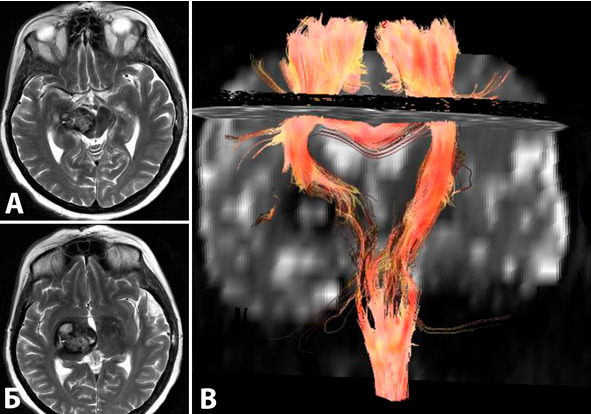

При диффузионно-тензорной МРТ возможна визуализация нервных волокон, образующих тракты (рисунок 20). С учетом данных такого исследования можно планировать операционный доступ, прогнозировать возможность восстановления неврологических функций. Исследование было выполнено у 4 больных. Все больные имели каверномы глубинной локализации. Во всех случаях удалось визуализировать проводящие пути. Известным ограничением метода является сложность визуализации проводников при отеке мозгового вещества (у обследованных 4 больных не встречался).

Рисунок 20. МРТ больной с каверномой базальных отделов правого зрительного бугра и среднего мозга. При МРТ-трактографии выявлено оскуднение проводящих путей в правой половине среднего мозга, их смещение кпереди и медиально. А, Б – МРТ в Т2 режиме, аксиальная проекция, В – реконструкция проводящих путей.